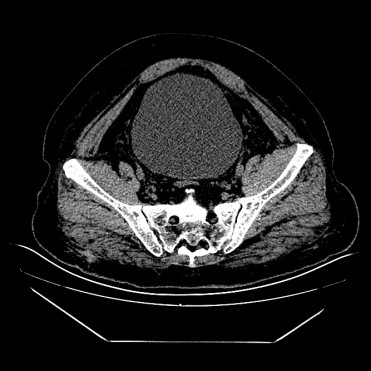

尿潴留是指膀胱内充满尿液却无法正常排出的病理状态。根据发病急缓可分为急性和慢性两类:

- 急性尿潴留:突然无法排尿,膀胱迅速充盈,伴随下腹部剧烈胀痛,需紧急处理;

- 慢性尿潴留:排尿困难、尿线变细、残余尿增多,症状持续超过 3 个月。

若出现上述症状,建议及时做泌尿系超声检查,通过测量残余尿量(正常应<50 ml)和肾脏形态,判断是否存在尿潴留及肾损伤。